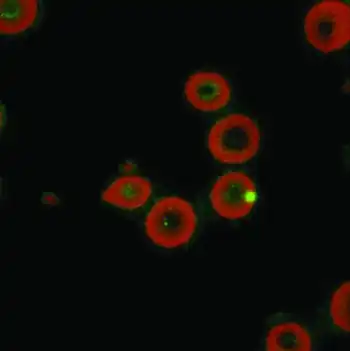

| Laser confocal microscopy shows intraerythrocytic location of Bartonella quintana[2] | |

The disease is caused by the bacterium Bartonella quintana (older names: Rochalimea quintana, Rickettsia quintana), found in the stomach walls of the body louse. Bartonella quintana is closely related to Bartonella henselae, the agent of cat scratch fever and bacillary angiomatosis.[6][1][3]